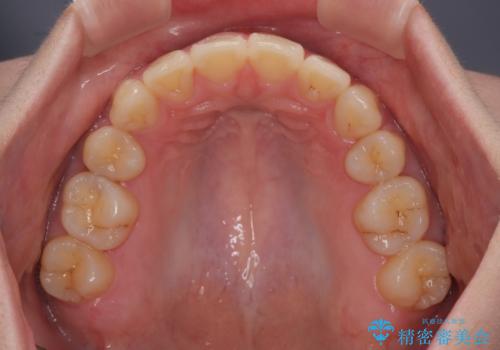

- 下顎の前歯が上顎の歯肉に咬みこむくらいに突出した上顎前歯を気にして来院された患者様です。

口元の突出感はないものの、上顎前歯が前方に傾斜して突出しており、前後に大きなズレがあり非常に深い咬み合わせとなっていました。

前突間を改善するため、上顎左右の第一小臼歯を抜歯してワイヤー装置にて矯正治療を行うこととしました。

深い咬み合わせは上顎前歯を引っ込ませる大きな障害となるため、咬み合わせの改善が非常に重要となります。やや期間はかかりましたが、当初狙った通りの仕上がりで治療を終えることができました。